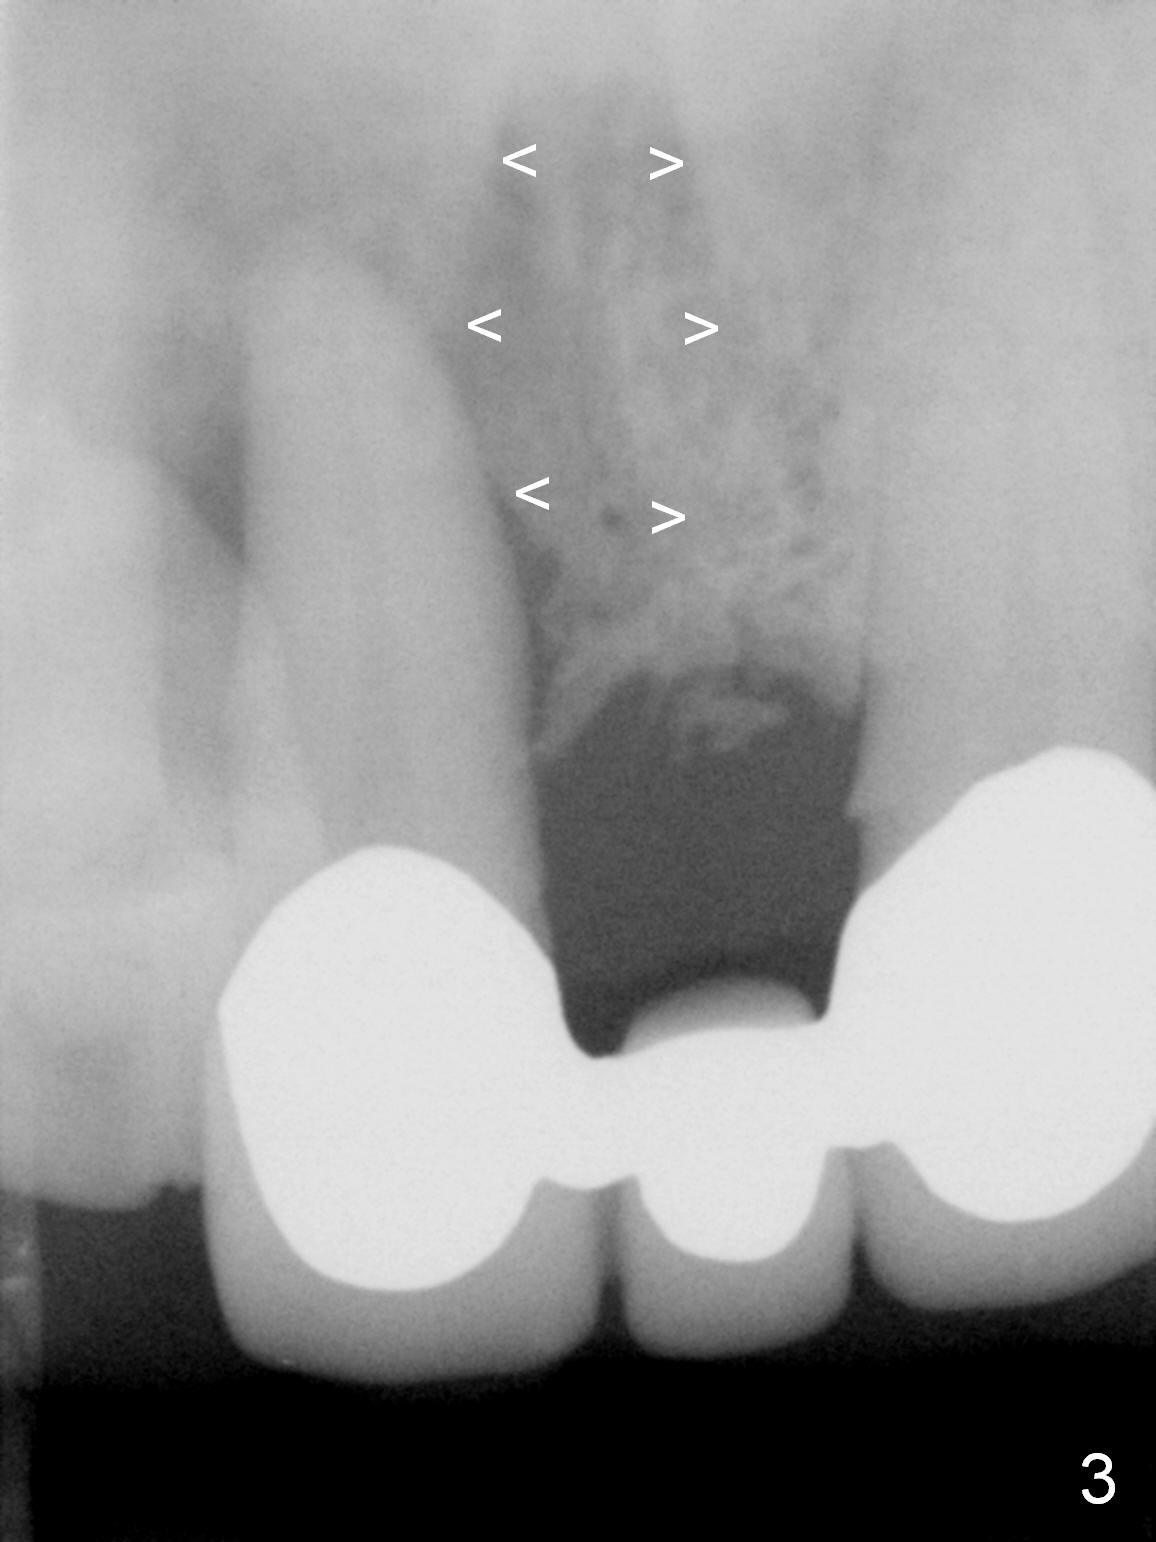

The 74-year-old patient is excited about having 3 implants placed without discomfort (1,2). He wants to take care of a loose FPD spanning from #8 to 9 (Fig.1). It appears that #8 is non-salvageable (Fig.2 * with deep pockets). There is severe bone loss around the affected tooth (Fig.3; Osteotape is expected for buccal and lingual defects). In addition, the Incisive Canal is abnormally large (arrowheads). The coronal end of a 4.5x20 mm implant and a 3.5x5 mm abutment will be slightly deviated mesially (Fig.4), since the 3-unit FPD will be converted to 2 single unit crowns. Surgical guide is ready. The 1st step is to section between #8 and the pontic (Fig.5; green outline: implant; red: abutment). If primary stability is low, the immediate provisional (Fig.8 white area) will be bonded the tooth #7 and the pontic as a supplementary measure (blue areas). Once the implant is osteointegrated, the distal portion of the pontic (Fig.7 *) will be removed. Acrylic is added to the mesial portion of the provisional (Fig.8 *) so that the papilla (P in Fig.7) will be pushed mesially and incisally (Fig.8 arrowheads). The step will be repeated a few weeks later (Fig.9). It could be done bilaterally at the same time by removing #9 crown and converting to the provisional. Finally the pontic will be removed. Two relatively wide crowns will be fabricated if the patient is satisfied with the provisional.